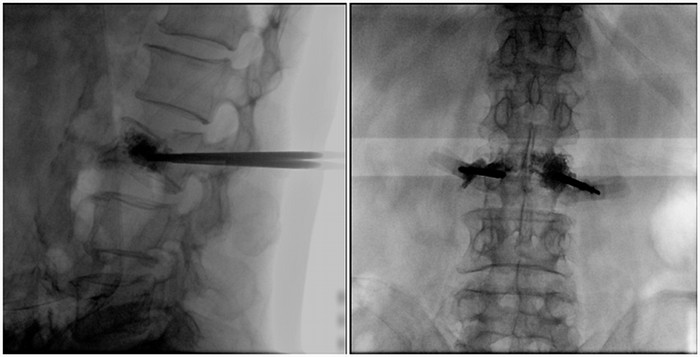

術中切口5毫米,在大平板C臂機的透視指引下,確定了進針的方向及進針的深度。經椎弓根向椎體置管,建立通道,插入骨擴張器(球囊)。球囊擴張恢復椎體高度,并在椎體內形成空腔,確定骨水泥的注入劑量,并注入骨水泥觀察其擴散情況。

大平板C臂機臨床圖像